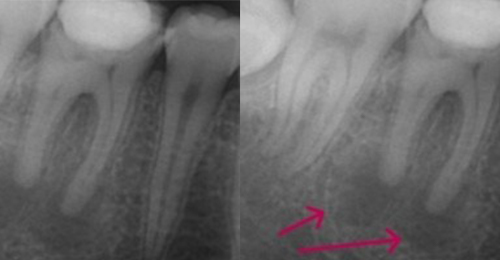

こちらのレントゲン写真を見てください。どちらかの歯医者さんで神経を取っています。根管に入れる薬は白く映ります。赤矢印部分です。一番右側が模式図ですが、青い部分が薬、根っこの先の赤点が化膿している部分です。

薬がほとんど入っていないのがわかります。黄矢印部分です。青矢印まで薬が入らないといけないのですが、全く入っていません。その結果、根っこの先が黒くなっています。膿が貯まって化膿すると黒く写ってくるのです。

よく手抜きをしたのですかと聞かれます。おそらく手抜きではありません。担当した先生はベストを尽くしたと思います。ベストを尽くしても、抜髄は大変難しいので、これが精一杯だったのでしょう。

別な歯科医院で治してもらいました。薬が根の先まで入っているのがわかります(黄矢印)。 根尖の黒い影が消失しています(赤矢印)。骨が再生すると白く写るようになります。

①の写真はどちらかの歯医者さんで神経を取ってもらったレントゲン写真です。根っこの中に薬が全く入っていません。

②の模式図で青く描かれている部分が薬です。

根の先を見ると小豆ぐらいの大きさの黒い影が見えます。根の中でばい菌が繫殖し感染を起こすとこのような黒い影ができます。黒い影の部分は膿(ウミ)が貯まっています。こうなると腫れて痛みが出てくるのです。

③、④の写真はそれを治した後のレントゲン写真とその模式図です。白く映っている薬が根の先まできちんと入っているのが確認できます。そして根の先にあった黒い影が消えているのが分かります。根の先の炎症が治って、骨が再生すると白く映るのです。

実はこのケース、歯医者さんの神経を取る治療でこのような根っこの病気になってしまったのです。そこでこの患者さんは神経を取った歯医者さんではなく、別の歯医者さんに受診して、根っこの治療をして治したのです。